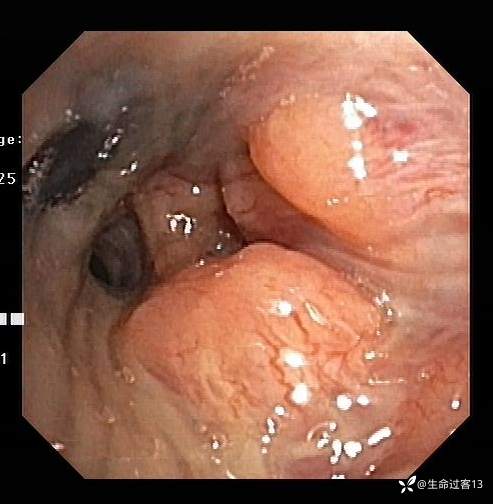

后行纤维支气管镜,如下:右上叶开口变异(未探及右上叶尖段开口);左主支气管远端1-5点钟方向及左上叶开口粘膜突起、肥厚增生,表面粗糙、凹凸不平,左上固有叶、舌叶开口狭窄、粘膜肥厚,其亚段窥探不清,左下叶开口通畅、粘膜光滑,双侧支气管散在碳末沉积。于左上叶(固有叶、舌叶)灌洗(灌洗量60ml,回收量50ml),灌洗液浑浊含痰液(送检培养+药敏、抗酸染色、脱落细胞、结核菌培养、Xpert),于左上叶开口粘膜肥厚处活检(送检病理)、刷检2次(送检细胞学+细菌学)。